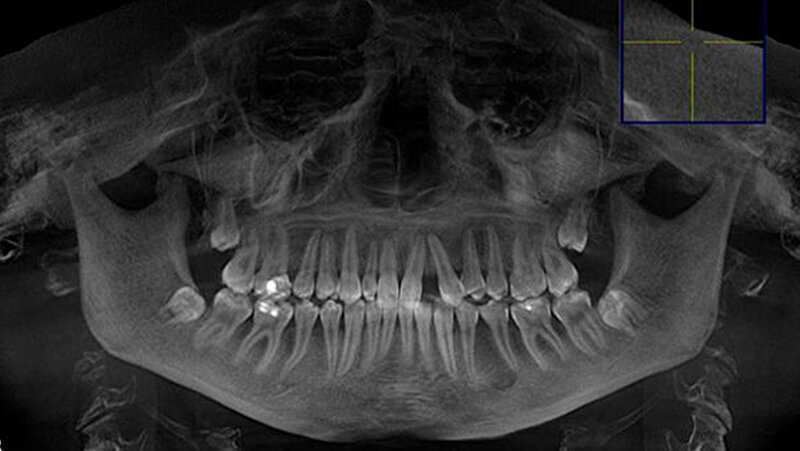

Eine 20-jährige Patientin stellte sich erstmalig zur Implantat- und Distraktionsberatung in unserer Abteilung für Mund-, Kiefer- und Gesichtschirurgie vor. Diagnostisch lagen eine mandibuläre Retrognathie, retinierte und verlagerte Zähne 18, 28, 38 und 48, ein Zapfenzahn 12, ein fehlender Zahn in regio 022, eine Mittellinienverschiebung und ein Engstand der Oberkieferfront vor (Abbildungen 1a bis d). Im Rahmen der klinischen Untersuchung und basierend auf dem Auswertungsergebnis der Digitalen Volumentomografie (DVT) führten wir bei der Patientin im Hinblick möglicher therapeutischer Maßnahmen eine differenzial-therapeutische Beratung durch.

Klinisch als auch radiologisch lag eine konvergierende Wurzelstellung der Zähne 21 und 23 vor. Eine unkomplizierte implantatprothetische Versorgung der Lücke 022, das heißt ohne Verletzung der benachbarten angulierten Zähne, erschien nicht möglich. Die Schwierigkeit bestand darin, die Lücke 022 durch körperliche Bewegung der Zähne zu öffnen, was sich bislang mittels festsitzender Apparatur als frustran erwiesen hatte. Der Patientin wurde aufgrund der vorliegenden Diagnose eine parodontal akzelerierte osteogenetische Orthodontie (PAOO) im Bereich des linken Oberkiefers empfohlen.

Darüber hinaus wünschte sich die Patientin, auch die Lücke mit dem Zapfenzahn 12 zu öffnen, damit weitere Korrekturen aus ästhetischen Gründen durchgeführt werden konnten. Auf den Zapfenzahn 12 sollte eine entsprechend größere Krone gesetzt werden oder gegebenenfalls eine Extraktion und eine Implantation erfolgen. Wir stellten der Patientin frei, auch dort das PAOO-Verfahren einzusetzen. Die Durchführung beider Korrekturen erschien in Vollnarkose und mit gleichzeitiger Entfernung der Weisheitszähne indiziert.